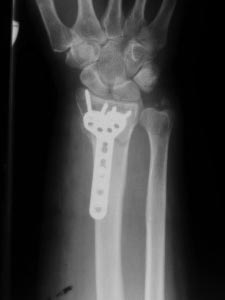

Перелом в "типичном месте" , Вопрос о фиксации шиловидного отростка

локтевой кости...

Оскольчатый перелом дистального метаэпифиза лучевой кости со смещением

отломков. Вопрос по поводу фиксации шиловидного отростка локтевой кости

Хотелось бы узнать мнения и аргументы. Надо ли фиксировать вообще?, если

да, то чем? и почему? Надеюсь на помощь коллег.